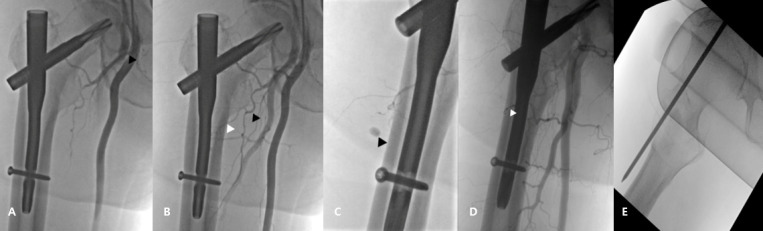

股骨粗隆间骨折引起的血管损伤是罕见的,但可导致严重的并发症。一例医源性损伤的外侧旋股动脉降支的病人接受手术固定股骨粗隆间骨折。损伤可能发生在使用导针插入钉入点的过程中。术后10天出现临床症状,经皮栓塞治疗成功,无重大并发症。本病例强调在髋关节内钉过程中使用导针可导致假性动脉瘤。外科医生可以通过获得髋关节的侧面和正前方视图来避免这种并发症。证据等级:IV,病例报告。

Vascular injuries associated with femoral intertrochanteric fractures are rare but can result in serious complications. A case of iatrogenic injury to the descending branch of the lateral circumflex femoral artery in a patient who underwent surgical fixation of an intertro-chanteric femoral fracture is presented. The injury possibly occurred during the creation of the entry point for nail insertion using a guide pin. Clinical symptoms emerged 10 days postoperatively and were successfully managed with percutaneous embolization, without major complications. This case highlights that pseudoaneurysms can develop as a result of guide pin use during hip nailing procedures. Surgeons can avoid this complication by obtaining lateral and anteroposterior views of the hip. Level of Evidence: IV, Case Report.